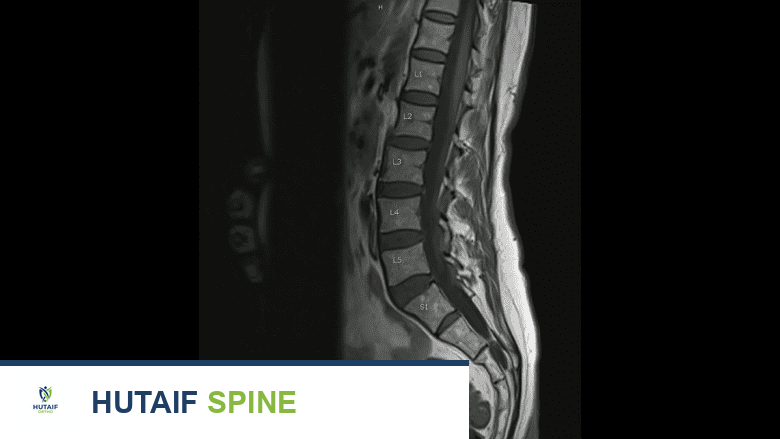

يوفر التصوير بالرنين المغناطيسي معلومات دقيقة عن الأنسجة الرخوة والهياكل العظمية للعمود الفقري.

التصوير بالرنين المغناطيسي MRI Scan

يُعد التصوير بالرنين المغناطيسي (MRI) الطريقة الأكثر شيوعًا لتصوير أورام العمود الفقري. يوفر معلومات دقيقة للغاية عن الأنسجة الرخوة والهياكل العظمية للعمود الفقري باستخدام طاقة المجال المغناطيسي لإنشاء الصور. نظرًا للطاقة المغناطيسية، لا يمكن للمرضى الذين لديهم أنواع معينة من الغرسات المعدنية أو الأجهزة الأخرى (مثل جهاز تنظيم ضربات القلب) إجراء التصوير بالرنين المغناطيسي، ويُوصى لهم بدلاً من ذلك بإجراء فحص CT مع صبغة تباين.